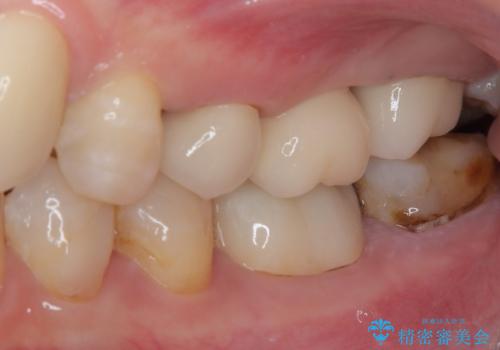

前歯をブリッジとするか否か、非常に悩まれていらっしゃいましたが、術前と比べてものが挟まる感覚がなくなったとのことで、大変満足されていました。

インプラントが必要となった奥歯は、インプラントが埋入できないほど隣の歯の根尖病変が非常に大きかったため、根管治療を行ったうえで半年ほど待ち、骨が再生したことを確認してからインプラントを埋入しました。期間は長くかかりましたが、大変良い仕上がりとなりました。